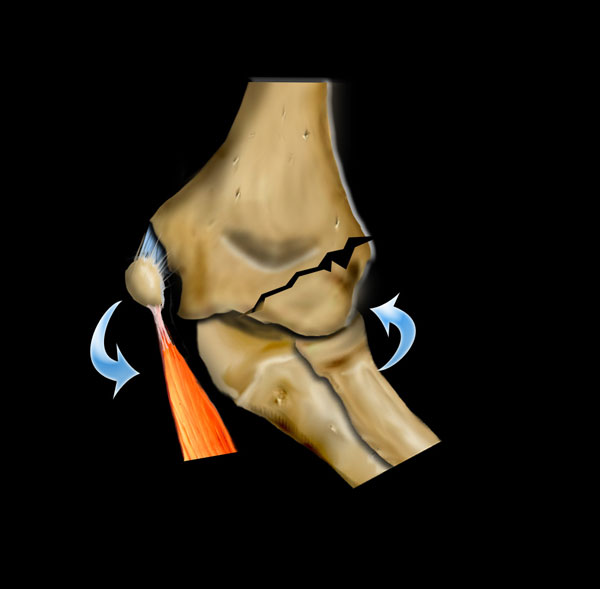

Gãy xương trên lồi cầu được phân loại theo Gartland.

Gãy xương loại I theo Gartland thường khó nhìn thấy trên X-quang do chỉ có di lệch tối thiểu.

Hầu hết các gãy xương này bao gồm gãy xương kiểu cành xanh hoặc gãy xương kiểu vỏ cây.

Dấu hiệu duy nhất gợi ý chẩn đoán có thể là dấu hiệu đệm mỡ dương tính.

Những bệnh nhân này được điều trị bằng bó bột.

Trong gãy xương loại II theo Gartland, có sự di lệch nhưng vỏ xương phía sau vẫn còn nguyên vẹn.

Có thể có một số xoay. Những gãy xương này cần nắn chỉnh kín và một số trường hợp cần cố định xuyên da nếu bột dài cánh tay không giữ được kết quả nắn chỉnh một cách thỏa đáng.

Gãy xương loại III theo Gartland là gãy xương di lệch hoàn toàn và có nguy cơ liền xương lệch và biến chứng thần kinh mạch máu (hình).

Những trường hợp này cần được nắn chỉnh bằng phương pháp kín hoặc nếu cần thiết bằng phương pháp mổ hở. Cố định được duy trì bằng hai đinh bên ngoài hoặc kỹ thuật đinh chéo trong-ngoài.

Gãy xương trên lồi cầu (4)

Liền xương lệch sẽ dẫn đến biến dạng ‘báng súng’ điển hình do xoay hoặc không chỉnh đủ tình trạng sụp đổ phía trong.

Di lệch ra sau ngoài của mảnh gãy xa có thể liên quan đến tổn thương bó mạch thần kinh bị di lệch qua mỏm gai hành xương phía trong.

Tổn thương thần kinh hầu như luôn dẫn đến chấn thương thần kinh tạm thời (neuropraxis) tự hồi phục trong 3-4 tháng.

Tổn thương mạch máu thường dẫn đến bàn tay mất mạch nhưng vẫn hồng hào.